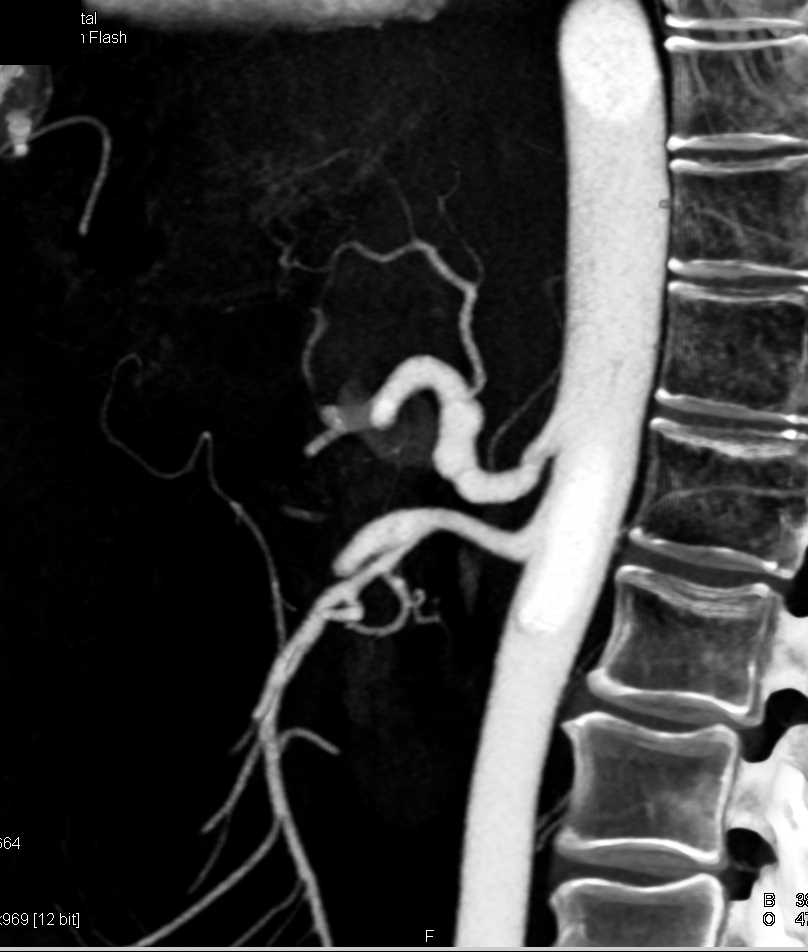

Aneurysm of the Celiac Artery